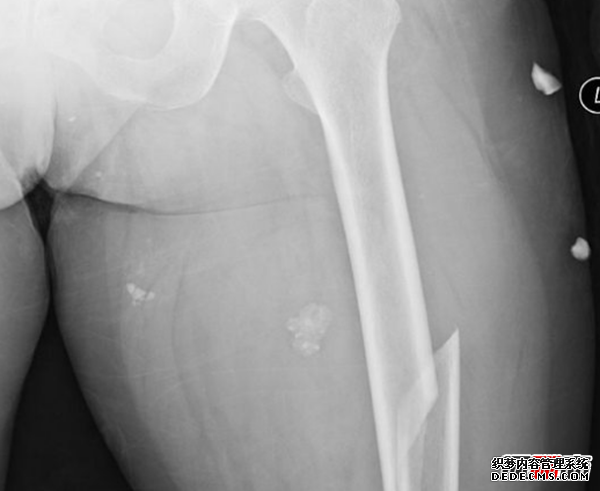

7、股骨骨折

股骨或大腿骨是人體中最大的骨骼,股骨骨折是人們可能經(jīng)歷的最痛苦的骨折。 即使在愈合過(guò)程中也是艱巨的,通常需要四到五個(gè)月的時(shí)間,并且在恢復多年后可能會(huì )受到某些因素的持續影響。